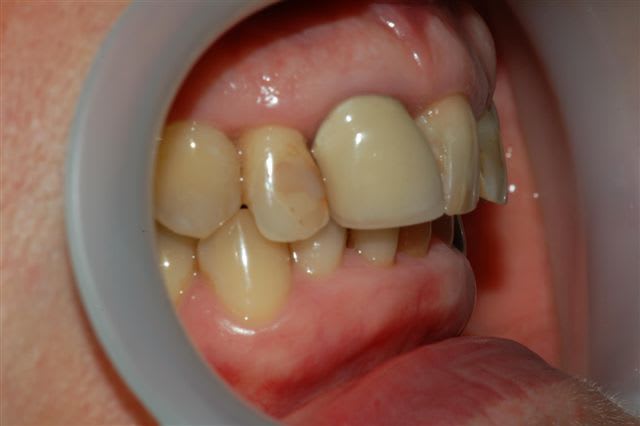

voici un cas traité en dentisterie globale à l'aide du laser en paro et du cerec en occluso, le cas à été terminé en 2010, cette semaine examen microbiologique de routine avec maintenance paro, il n'y a plus de flore pathologique dans la bouche de cette patiente

Emma